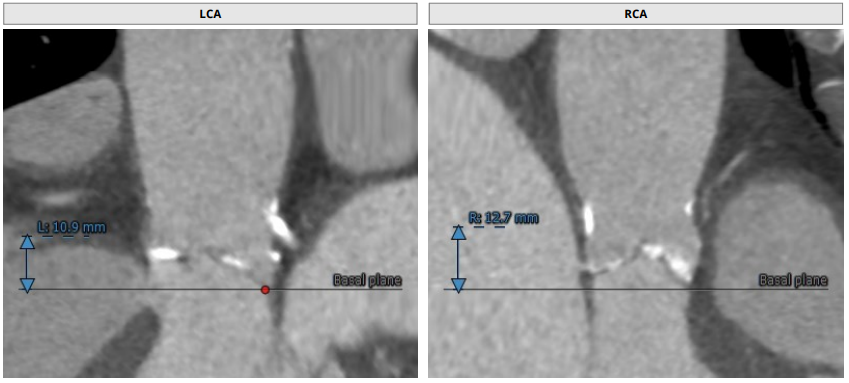

术前CT分析:

· 三叶瓣,中度钙化。整体结构呈上小下大,法式窦结构小,左冠瓣叶长度较长,流出道大。

· 冠脉严重钙化、提示严重冠心病。

· 难点:选择大号瓣膜担心冠脉风险,选择小号瓣膜担心瓣周漏。

瓣环平均直径:24.0mm,左室流出道平均直径:25.2mm

左冠窦:25.5mm,右冠窦:22.6mm,无冠窦:28.7mm,

窦管交界处:22.9mm

升主未见明显增宽:34mm,心脏角度:41°

钙化积分:501mm³,中重度钙化

左冠高度:10.9mm,右冠高度12.7mm

心室明显增大